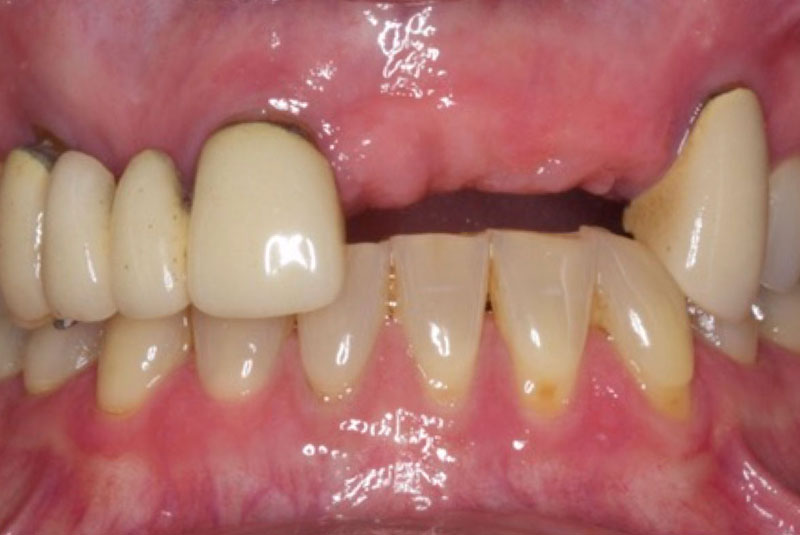

The patient had her implants placed 20 years ago. Four implants, particularly in the maxilla, were not positioned ideally for me to utilize and restore, while the four implants in the mandible were outdated and no longer functional. The patient's primary concern is to restore both function and aesthetics.

All on 6: Facial cut back (PFZ) Zirconia Full arch prosthesis for Maxilla and Mandible Before & After